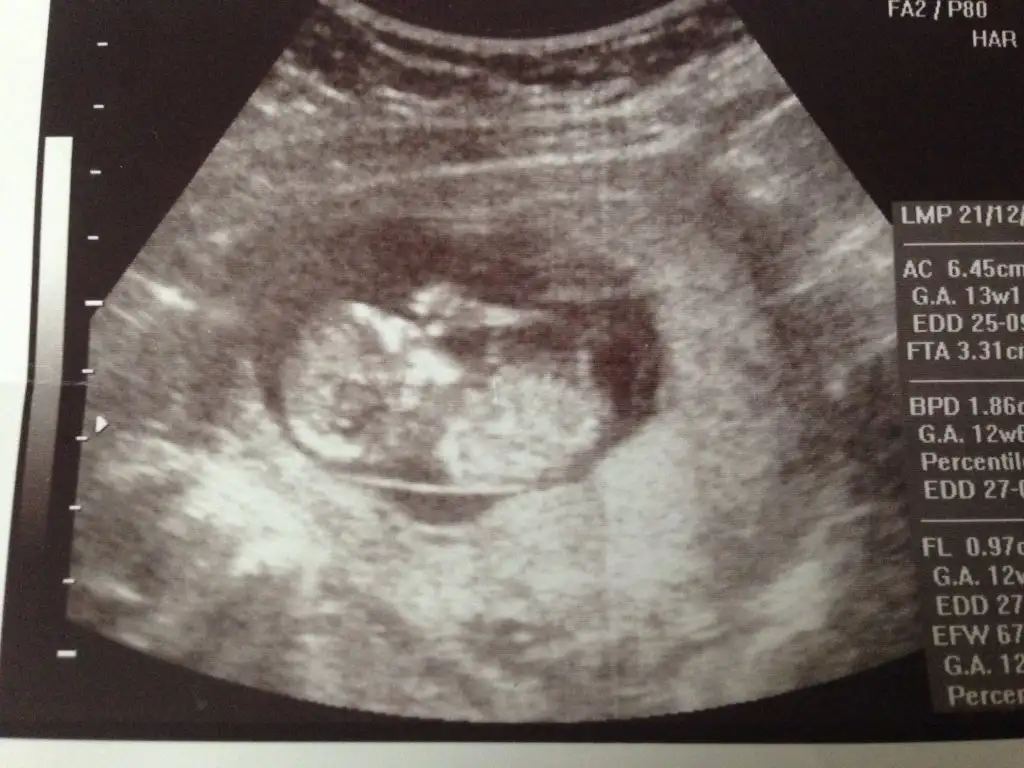

Bir süredir hastaydım. İşler de çok yoğun iş yerinde pek giremiyorum. Biraz kahverengi lekelenmem olmuştu. Normalde 16. haftada gidecektim ama, doktor gel bakalım dedi. Dün gittim. 14+6 çıktı. Doktor %90 erkek dedi :) Bana da gösterdi. Baya baya erkek yani aslında :KK48: ama kordonla falan karışabiliyor bazen dedi. 16'da karışmayacak duruma gelir:KK48: net söyleriz dedi. Yalnız tam gördüğü anı fotoğraflamadı. Diğer fotosu da net değil. Sırtı görünüyordu zaten, çekmedim fotosunu. Eski yüklediklerimi bir daha yükliyim kızlar. O zaman kız diyen de vardı erkek de. 2. fotoya genelde kız demiştiniz galiba. Bakın bakalım :))

• Bebişim 13+2.webp

Bebişim 13+2.webp

32,4 KB · Görüntüleme: 167